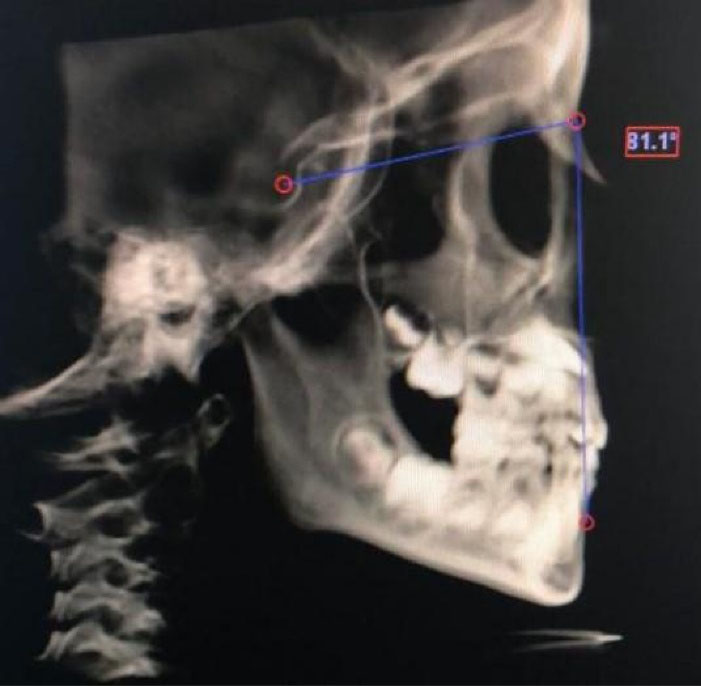

Figure 2.

Measurement of SNA angle.

| SNA | The angle created between sella, nasion, and A points |